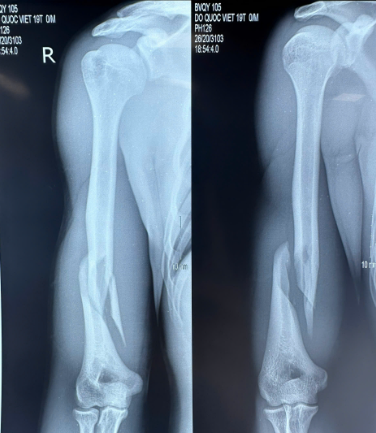

Điển hình trường hợp bệnh nhân nam, 19 tuổi, nhập viện trong tình trạng đau chói và mất vận động cánh tay sau khi vật tay. Tại khoa Chấn thương Chỉnh hình, Bệnh viện 19-8, qua đánh giá lâm sàng và phim XQ của người bệnh, BSCKII Đỗ Việt Sơn (Phó trưởng khoa Chấn thương Chỉnh hình, Phẫu thuật Tạo hình và Y học thể thao) nhận định đây là trường hợp gãy phức tạp 1/3 dưới xương cánh tay, đồng thời loại trừ tổn thương thần kinh quay – một biến chứng thường gặp trong loại chấn thương này.

Trong tư thế vật tay, xương cánh tay phải chịu lực xoắn lớn. Khi kỹ thuật không đúng hoặc cố gắng quá mức, xương có thể bị gãy, thường gặp ở 1/3 dưới thân xương, ổ gãy thường chéo vát (theo chiều lực xoắn vặn), và có nhiều mảnh rời.